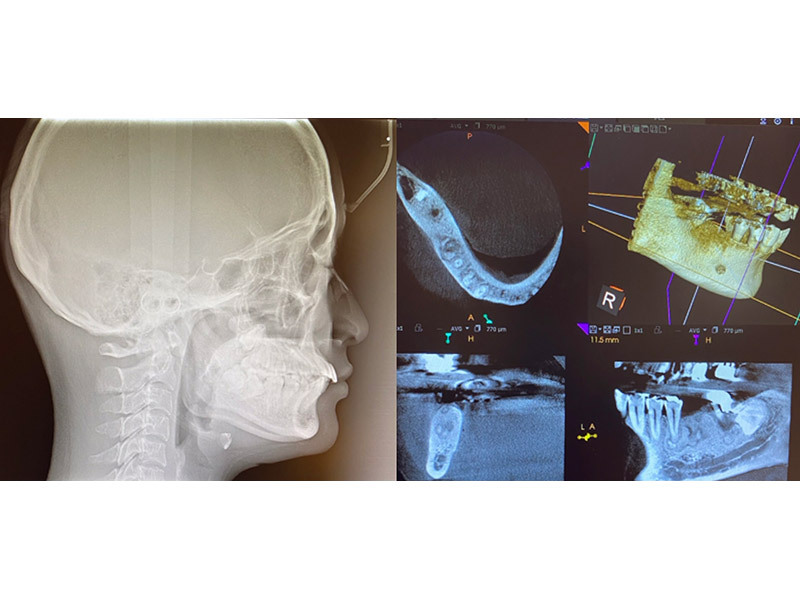

CT&セファロ

現在の高度な歯科治療を実践するためには、CTによる、インプラント 、外傷、根管治療あらゆる場面で3次元的診断が必要です。セファロ分析がなければ矯正治療も行えません。

当院ではより高度な診査を行うため、高性能なCTに入れ替えをおこないました。

CT

かつてのレントゲンと違い、低線量かつ必要な範囲に絞った撮影をすることができます。

X線画像を立体の状態で見ることができるので、より精度の高い診断が可能となり、治療に役立ちます。